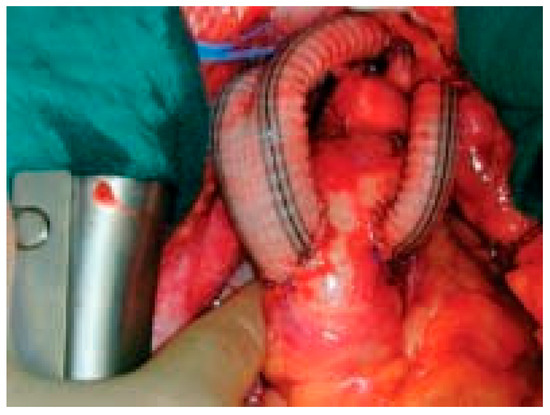

Une patiente de 31 ans souffrant d’une cardiopathie congénitale consulte car elle souhaite une grossesse [...]